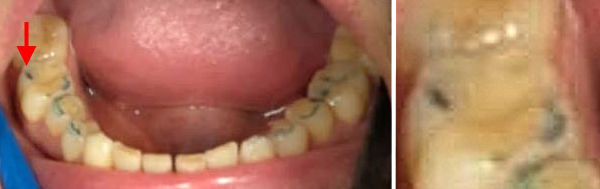

| Gerne empfehle ich Dr. Michael Bayer für Okklusionskorrekturen. Er arbeitet minimalinvasiv und behandelt auch Angstpatienten sehr schonend. Eine Spezialität von ihm ist der Aufbau von tief zerstörten Einzelzähnen direkt im Mund (mit dem Kunststoff IPS E-max Press). Nebenstehende Bilder zeigen den Wiederaufbau eines stark abgenützten Gebisses mit Kunststoff. | | |

Bei sehr stark abgenützten Zähnen wird beim Zubeissen der Abstand Kinn-Nase kleiner. Die Zähne sind nur noch 2-3 Millimeter hoch, und beim Essen wird häufig das Zahnfleisch verletzt. Dann sollte man nicht einschleifen, sondern bei allen Zähnen Komposit ansetzen und den Biss erhöhen.